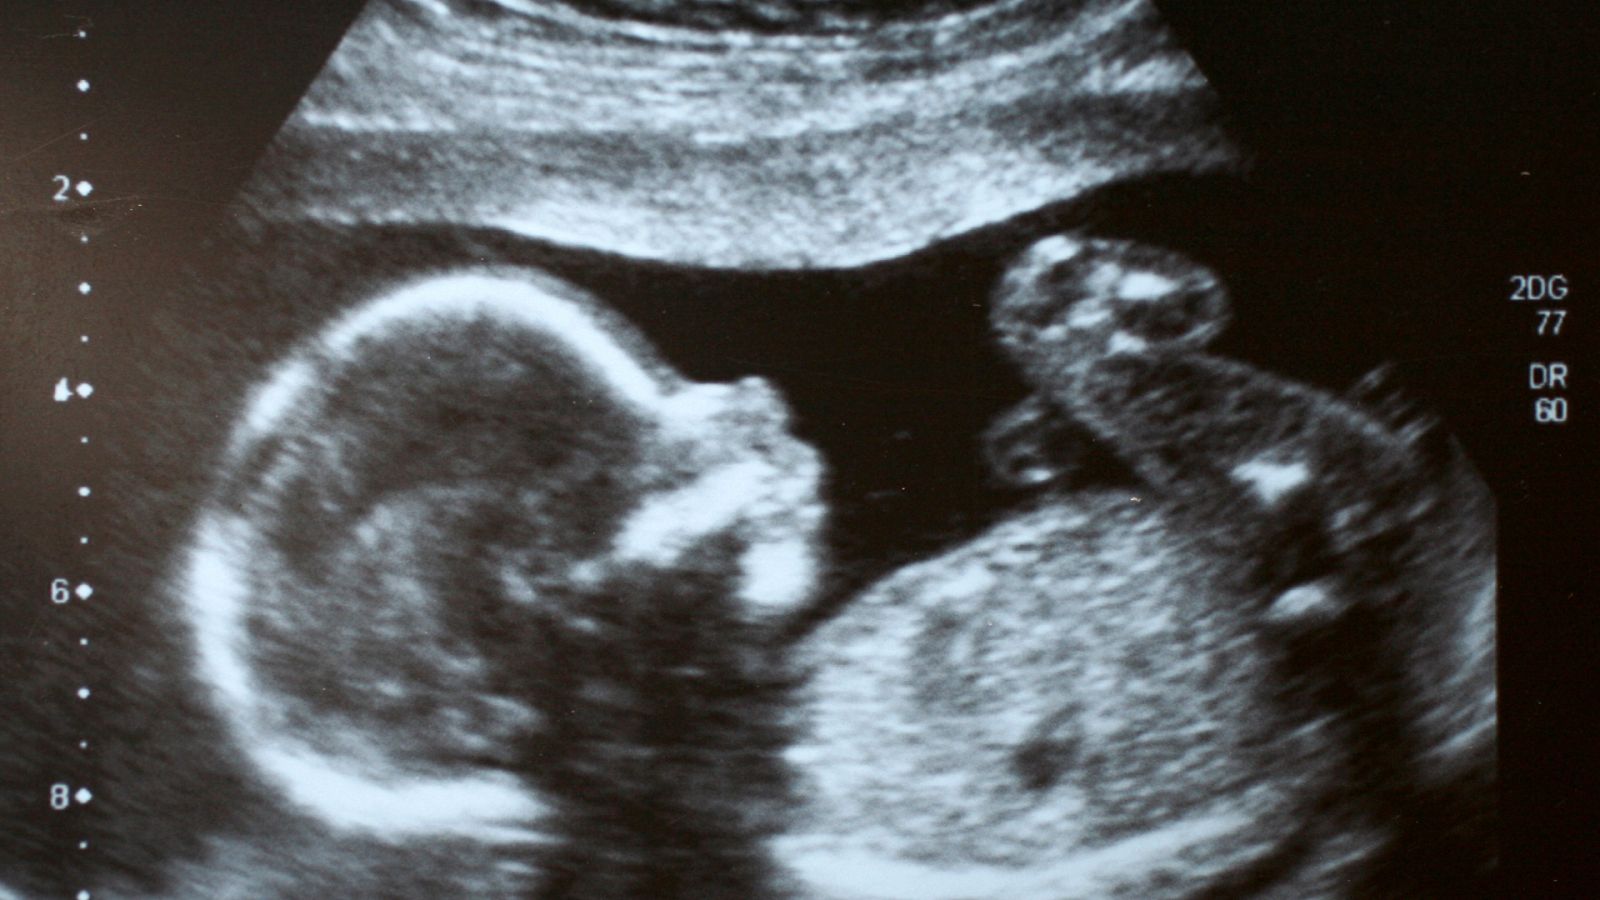

Raíz de 5 - Cómo se calcula el peso de un bebé a través de una imagen? - 03/07/23 - Escuchar ahora